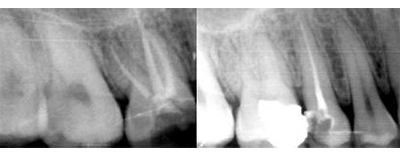

X线片显示:未根充,根尖区牙周膜略增宽。

术前X光片 术后X光片

常规根管治疗:去旧充填物,寻及四根管口,根测,扩孔,NITI预备,冲洗,封药。一周后必兰糊剂+冷侧压根充。预约两周后16冠修复。

经过详细的检查和精确的方案制定,医生为田先生进行了根管治疗手术。两周后,田先生感觉良好,右上后牙疼痛消失,上次治疗后无明显不适。牙齿不松动,牙龈无红肿。为了确保根管治疗效果,后又进行了二氧化锆全瓷修复。